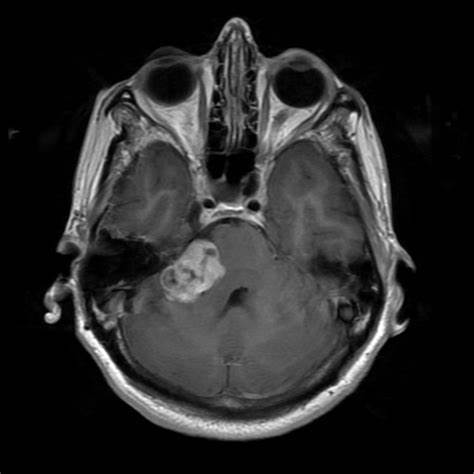

前庭神经鞘瘤听神经瘤

图片尺寸1280x1006